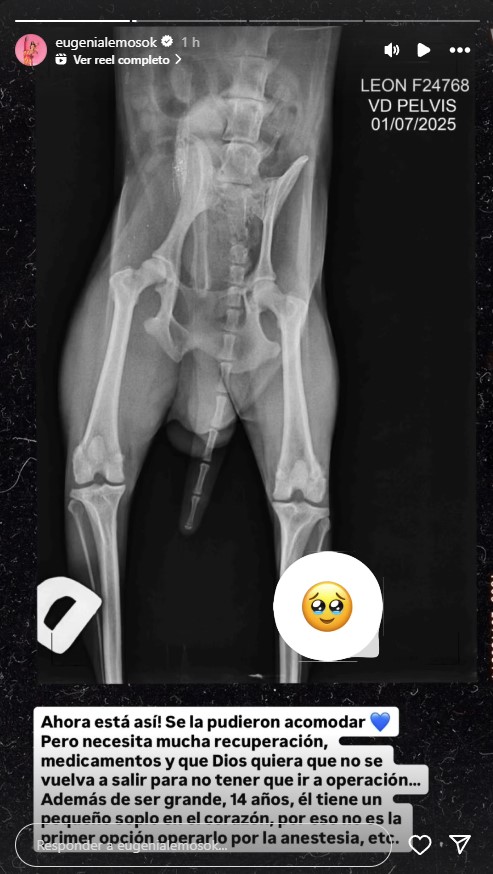

La creadora de contenido de moda publicó la radiografía que le realizaron a León, en la cual se le pudo ver la lesión que le descubrieron: "El martes llegamos de Buenos Aires y nos tocó correr todo el día porque Leonchi tuvo una luxación colofemoral, los 14 años no vienen solos".

Afortunadamente, el equipo médico pudo darle el tratamiento adecuado al perrito: "Ahora está así, se la pudieron acomodar, pero necesita recuperación, medicamentos y que Dios quiera que no se vuelva a salir para no tener que ir a operación".

También, Eugenia Lemos expuso los otros problemas de salud que tiene León: "Además de ser grande, 14 años, él tiene un pequeño soplo en el corazón, por eso no es la primera opción operarlo por la anestesia".